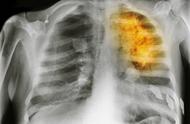

但是在这里提示,的的确确有抽烟的话患上肺癌的几率还是相当大的。X线检查通过X线检查可以了解肺癌的部位和大小,可能看到由于支气管阻塞引起的局部肺气肿、肺不张或病灶邻近部位的浸润性病变或肺部炎变。